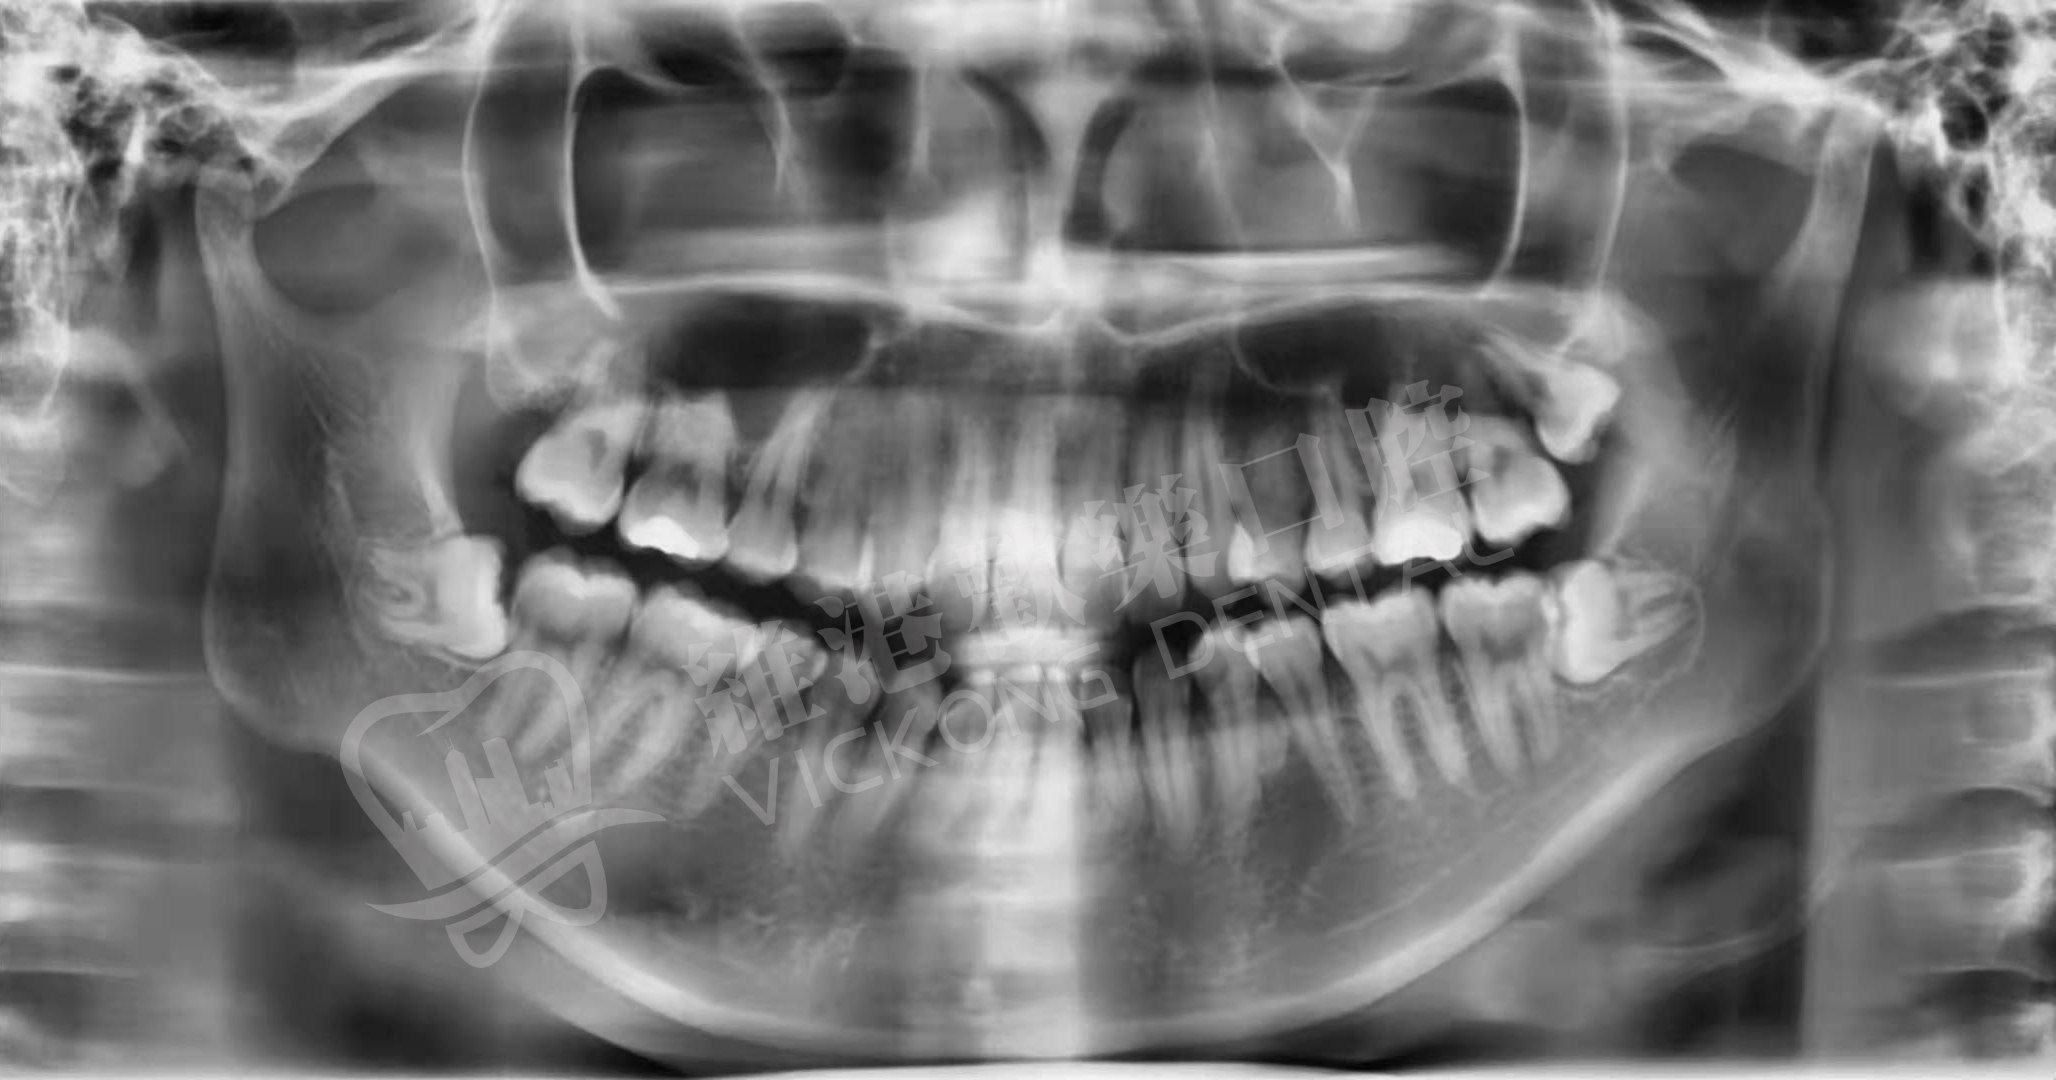

患者情況:共長了三顆智齒,下方兩顆都是阻生齒,並且兩顆都是水準阻生,是拔除難度比較高的一種阻生齒類型。

治療方案:今日先拔除左側兩顆智齒(微創拔除),下次復診再商量時間拔除右側下方那顆阻生齒。

治療情況:目前已經成功拔除兩顆智齒,等一周後可拆線,術後24小時內不要刷牙和漱口,儘量吃流食,少觸碰到傷口。

圖一 患者拔智齒前牙片